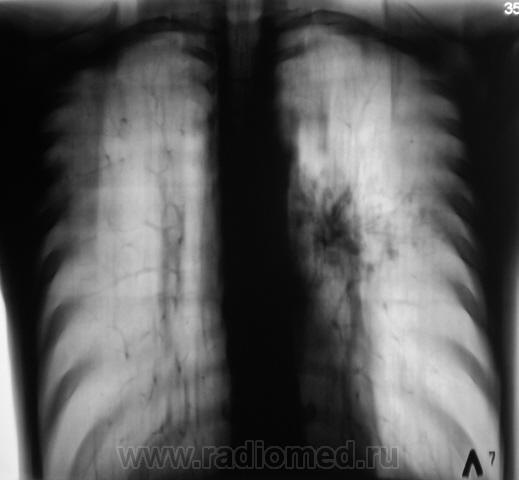

Мы вместе с коллегой фтизиатром долго сидели над этими снимками. Решили провести "противовоспалительное лечение", и провести контроль.

Так он раньше не наблюдался? От пробного неспецифич. лечения вреда не будет, а пользу можно поиметь.

Архив. Флюорограмма прошлого года - "норма"

верхушки,а так же все задние сегменты(2.6,,реже 10)наиболее типичная локализация туберкулеза,субплеврадьно.И если год назад была норма,это еще не не значит,что это не туберкулез,а поможет только в определении активности процусса.

Спасибо коллега за коммент. Вот, мы с коллегой фтизиатром, взвесив все "за" и "против", решили в течение 1 - 1,5 недель провести противовоспалительную терапию, а затем "решать вопрос". Архив, а именно, отсутствие изменений в прошлом году, также было учтено.

Пациент получает противовоспалительную терапию. Но, прибегает коллега фтизиатр - "палки", "палки", "палки"...

Берем на "контрольное" обследование перед госпитализацией в областное специализированное учреждение...